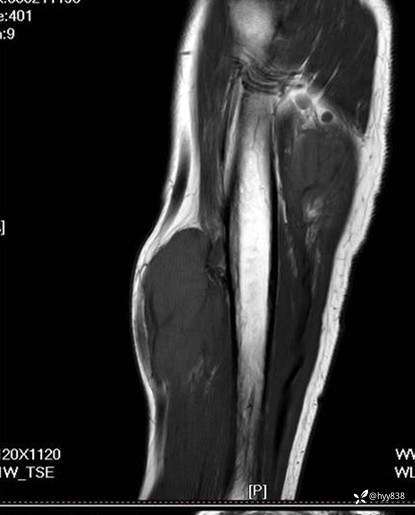

SAG T1WI+PDWI fs